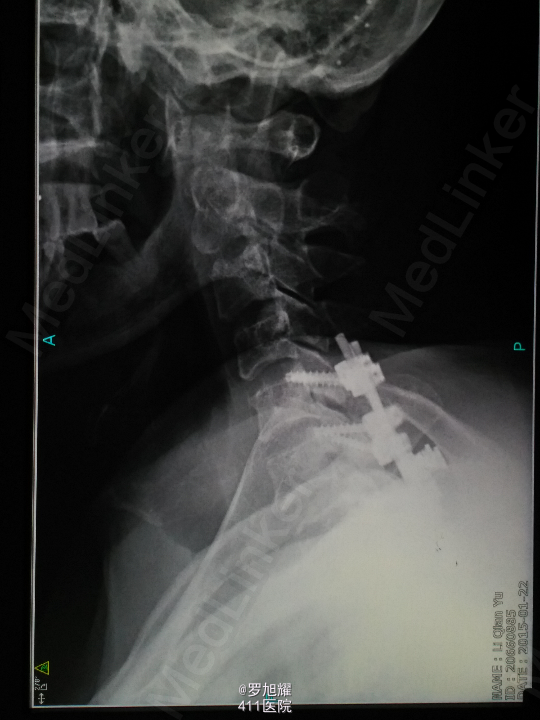

诊断:颈6/7骨折脱位伴高位截瘫。处理:立即甲强龙冲击、脱水、保胃、营养神经治疗。首选治疗方案是颅骨牵引复位后前路融合固定,较后路稳定,出血也少,和家属谈话后开始颅骨牵引复位,4kg起步,每半小时增加1kg直至14kg,调整颈椎屈伸位,再加用手法牵引仍不能复位。改用备选方案,急诊行后路切开减压撬拨复位内固定,术后瘫痪症状部分改善。随访3月双上肢前臂及手部感觉恢复,仅双手掌尺侧及小指感觉障碍,双侧三角肌、肱二三头肌肌力4-5级,腕关节屈伸、旋转肌力左侧3级,右侧3-4级,但各指肌力仍0级。

这里主要想讨论一下颈椎脱位闭合牵引复位的问题。 Mahale 等指出 , 下颈椎小关节突脱位复位后, 神经功能并发症最多见于手术切开复位 , 全麻下手法复位次之 , 颅骨牵引闭合复位最低 。作者认为, 切开复位最容易造成脊髓的直接损伤 , 而颅骨 牵引闭合复位所致脊髓功能恶化 , 主要是由于牵引方向不当, 从而加重了脊髓受压。此外 , 不论采取 何种方法复位 , 复位后脊髓水肿均是加重脊髓功能恶化的因素。 国内新桥医院骨科任先军等大重量颅骨牵引复位下颈椎小关节突脱位64例,成功60例,1例不全瘫患者复位后出现一过性左上肢根性痛加重,经脱水 、 激素治疗后缓解, 考虑可能系复位时神经根受到牵拉刺激所致。1例全瘫患者于复位后 24h 因呼吸衰竭死亡 , 其确切原因尚不十分清楚 。我们考虑可能与复位本身无直接相关 , 可能与复位后脊髓上行性水肿有关。 4 例未成功者中, 一例系呼吸困难 , 一例系关节突骨折 , 一例为陈旧性脱位 , 一例因不能耐受大重量颅骨牵引而终止复位。我们的结果表明 , 透视下大重量颅骨牵引复位是一种安全有效的方法 。 复位牵引重量平均为 27.5 kg ,最高达 40.5 kg , 远大于国内文献报道。 教科书上一般10-15kg,我加到14kg,辅以手法估计也有5kg,实在担心脊髓损伤风险,还是后路切开撬拨复位了。各位老师和同仁有什么建议和技巧,恳请点拨!